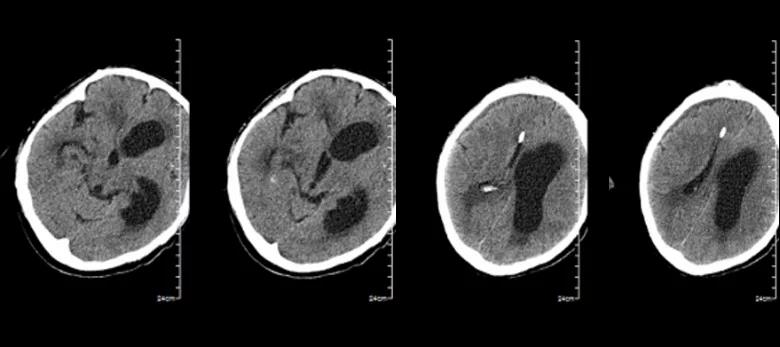

患者颅内感染明确,但仍缺乏病原学依据。抗生素方案调整为美罗培南针联合替加环素及斯沃针。后患者意识水平进行性下降,头颅MRI复查提示脑积水进行性加重。3月27日复查腰穿测压290 mmH₂O,脑脊液淡黄透明澄清。神经外科会诊后3月28日行右侧ommaya囊植入术并予穿刺引流,术后CT复查(图10):右侧额叶少量硬膜下积液,右侧脑室相对缩小,左侧脑室及第三脑室扩张,中线结构右偏。

图10. 3月29日头颅CT